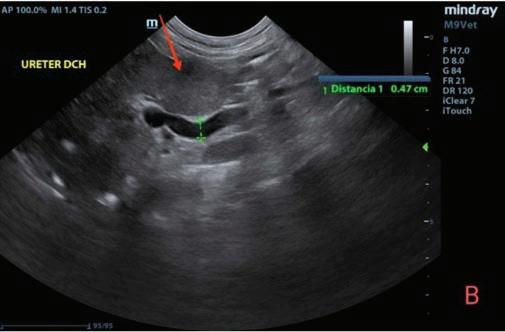

El segundo caso fue un perro mestizo de galgo y villano de 3 años y medio de edad que se presentó en enero de 2023 con un cuadro de excitación grave, ataxia, gemidos y sialorrea intensa que se muestra en los videos 1A-D. No presentaba antecedentes ni tratamientos previos.

En la exploración general, el paciente se encontraba cubierto de suciedad, barro, heces, orina y saliva. Presentaba taquipnea, sialorrea densa y edema del labio inferior derecho (Figs. 2 y 3). Adicionalmente, el animal mostraba prurito con signos de rascado intenso en tronco, cabeza y hueco axilar y se mantenía inquieto, con vocalizaciones y ataxia. Al contacto con el

En la anamnesis se confirmó su participación en una batida junto con otros 40 perros en enero de 2023. Como en el caso anterior se descartó la afectación por procesionaria del pino, irritantes, patologías orales y alimentación con jabalí o cerdo crudo. Ante el estado de sufrimiento del animal, el propietario decidió proceder a su eutanasia humanitaria y se remitió el cadáver al laboratorio.

A B C d

NEIKER confirmó la afectación por EA mediante PCR en encéfalo positiva y tonsila no concluyente (Anexo 2). La necropsia informó de intenso edema en la cabeza y zona intermandibular. Se observó alopecia por rascado en hocico, zona ventral del cuello y extremidades.

Figura 2. Intensa sialorrea en el caso 2. Figura 3. Edema de la mucosa labial (rascado) en el caso 2.